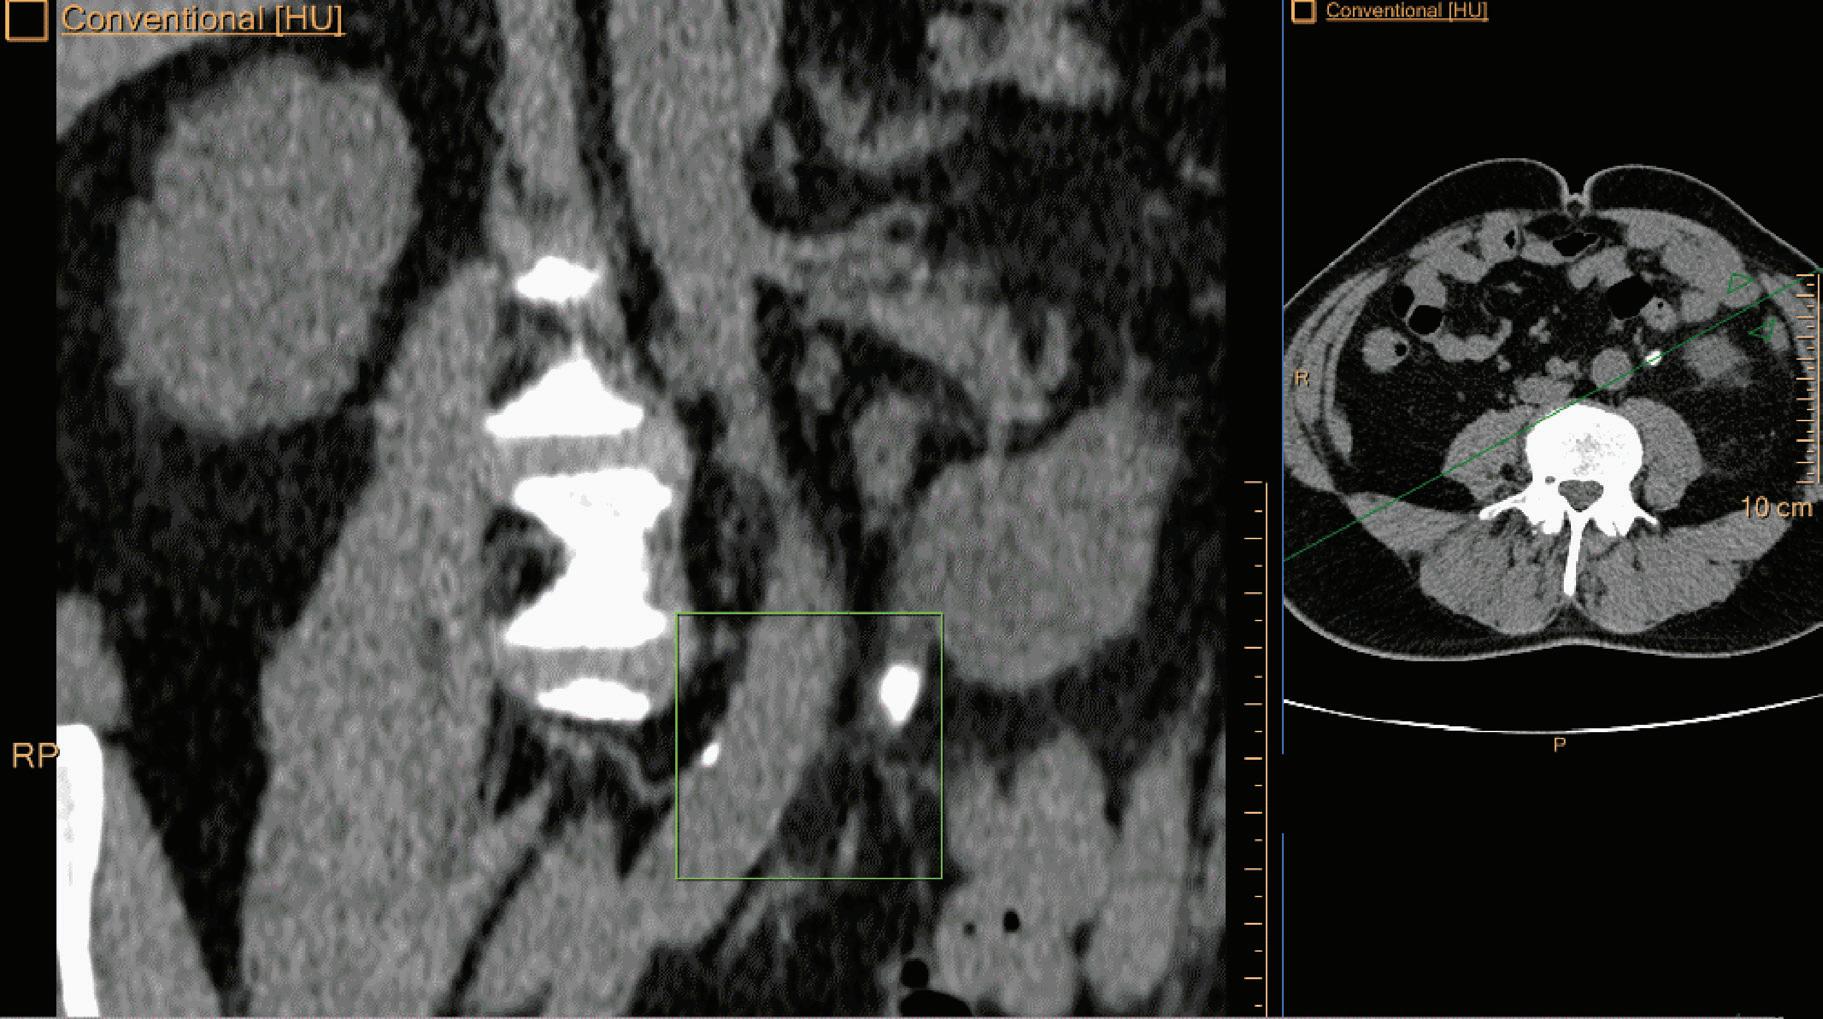

Calcium Suppression (CaSupp) [HU]

Are images that display the attenuation without the attenuation contribution of calciumbased materials.13 Same as the iodine suppression in VNC, but for various calcium-based material. A higher calcium suppressed Index (CSI) corresponds to a higher calcium composition weight (Figure 7).

As Alvarez and Macovski wrote, the optimal material base must be selected phenomenologically taking into account the energy range and the materials the X-ray beam is expected to transverse. If bone and water are chosen as the base materials for the decomposition, the information from the low and high attenuation data can be used to calculate the bone coefficients of the X-ray attenuation. These coefficients can then be used to create a bone image which allows the assessment of bony structures and calcifications. Alternatively, the water coefficients can be calculated to generate a soft tissue image where the bony structures are suppressed and which improves the visualization of structures previously hidden by bony anatomy. Any material pairs can be created from any other pairs as a linear transformation post-decomposition: a change of base. Other pairs of base materials with clinical relevance are iodine and calcium, iodine and water, or calcium and water. In cardiovascular imaging, the iodine images from an iodine-calcium pair can be of primary importance because they can help to better assess the iodinated lumen of the arteries which could be otherwise hidden by the presence of large calcified plaques. The water images from an iodine-water pair are ones in which all of the iodine is removed. These virtual non-contrast images (VNC) synthesize a pre-contrast scan.11,12 The water images from a calcium-water pair are ones in which all of the calcium is removed. These calcium suppressed images (CaSupp) can be used to improve the visualization of the bone marrow edema which is partially hidden by the presence of the bony structures in the conventional CT images.13